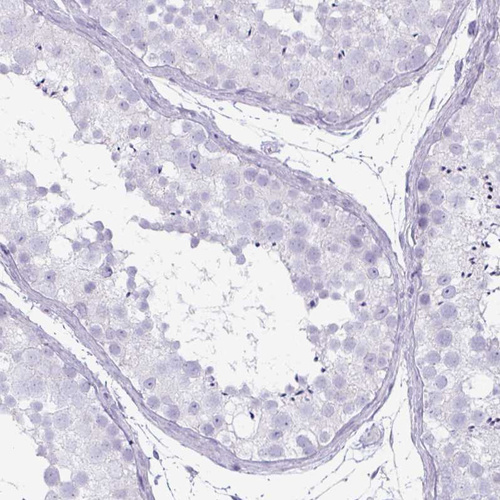

Immunohistochemistry analysis in human colon and liver tissues using HPA052787 antibody. Corresponding CLCA1 RNA-seq data are presented for the same tissues.